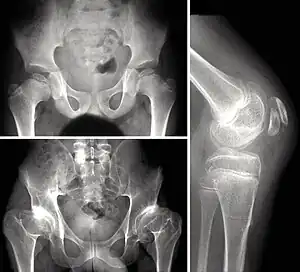

Children with autosomal dominant MED experience joint pain and fatigue after exercising. Their x-rays show small and irregular ossifications centers, most apparent in the hips and knees. There are very small capital femoral epiphyses and hypoplastic, poorly formed acetabular roofs.[1] A waddling gait may develop. Knees have metaphyseal widening and irregularity while hands have brachydactyly (short fingers) and proximal metacarpal rounding. Flat feet are very common.[2] The spine is normal but may have a few irregularities, such as scoliosis.

By adulthood, people with MED are of short stature or in the low range of normal and have short limbs relative to their trunks. Frequently, movement becomes limited at the major joints, especially at the elbows and hips. However, loose knee and finger joints can occur. Signs of osteoarthritis usually begin in early adulthood.[3]

Symptomatic individuals should be seen by an orthopedist to assess the possibility of treatment (physiotherapy for muscular strengthening, cautious use of analgesic medications such as nonsteroidal anti-inflammatory drugs). Although there is no cure, surgery is sometimes used to relieve symptoms.[18] Surgery may be necessary to treat misalignment of the hip (osteotomy of the pelvis or the collum femoris) and, in some cases, malformation (e.g., genu varum or genu valgum).[19] In some cases, total hip replacement may be necessary. However, surgery is not always necessary or appropriate.[20]